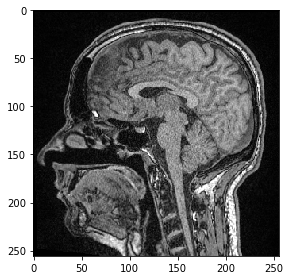

Interopérabilité avec clesperanto#

Ensuite, nous envoyons cette image d’un seul plan sur le GPU et la transformons en utilisant pyclesperanto

import pyclesperanto_prototype as cle

cle.select_device('RTX')

<gfx90c on Platform: AMD Accelerated Parallel Processing (2 refs)>

image_gpu = cle.push(image)

# define transform with #scikit image

from skimage import transform as tf

transform = tf.AffineTransform(scale=0.5, translation=[10,0])

transformed_image = cle.affine_transform(image_gpu, transform=transform)

cle.imshow(transformed_image, color_map="Greys_r")

c:\structure\code\pyclesperanto_prototype\pyclesperanto_prototype\_tier9\_imshow.py:14: UserWarning: The imshow parameter color_map is deprecated. Use colormap instead.

warnings.warn("The imshow parameter color_map is deprecated. Use colormap instead.")

../_images/de3fcfb06177c0049426480e12bd738ddf30a227e64865662437057637224755.png